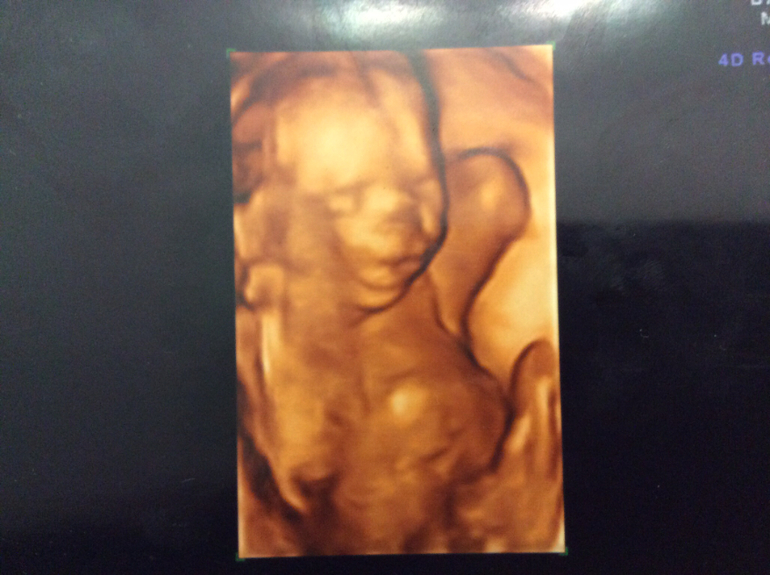

2 ой скрининг

Была сегодня на узи. Мальчик девочкой не стал))) все у него хорошо! Срок 20 нед и 3 дня. Весит уже 355 гр, сказали очень даже прилично. Не даром видно я 2 кг набрала за 26 дней. Надеюсь все же поменьше, тк была в платье в пол и оно довольно тяжелое))) сидит на попе, руки под головой- как на пляже. Говорят детки довольно редко так лежат. Видно в папу весь, его любимая поза))) Есть однократное обвитие, но тк срок еще маленький и все равно КС, то побарабану)) Были у меня подозрения, что карапузяка икает, но думаю срок еще маленький, наврятли. А тут чувствую заикал, гляжу на экран- точно, икает! Так забавно подергивается, рот открывает))).

Что не очень хорошо плацента опускается вниз( В 15-16 нед была на 3,3 см выше внутреннего зева, а теперь на 1,7 см... Через месяц на контроль, главное чтоб дальше не опускалась!!! Да и прикрепился он практически на шве(((